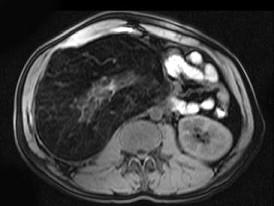

问题 男,30岁。右侧腹部包块渐增大,伴胀痛1年余。MRI检查见巨大包块,最可能的诊断是 ( )

选项 A、右肾巨大血管瘤 B、右肾错构瘤 C、右肾髓样脂肪瘤 D、右肾畸胎瘤 E、右侧肾上腺腺瘤

答案 C